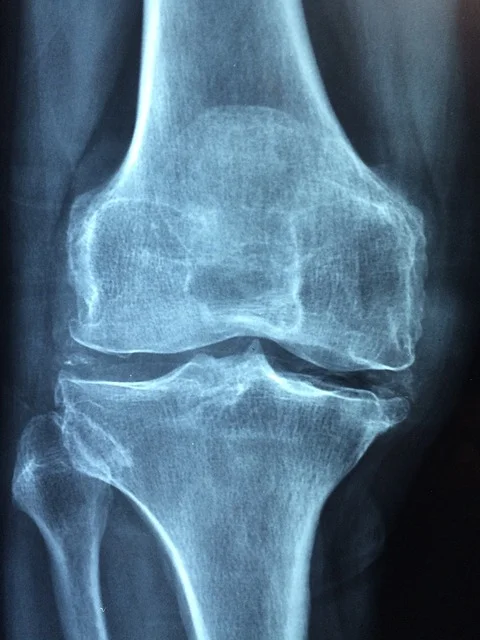

Photo of xray for knee Injury

Runners Knee

Most knee pain problems have nothing to do with the knee…..??

Patellofemoral Pain Syndrome is a very painful condition where the patella (knee cap) moves or tracks away from the articulations of the knee bones - the research shows the patella sliding outside the grooves but in reality it is the bones that move out of synch which is the problem! So ‘stiff’ or ‘hyper mobile’ feet/hips can normally be found to be the culprit. It is the most common overuse knee injury amongst runners and it can account for up to 40% of the knee complaints in sports medicine clinics. There are other types of knee pain which stem from trauma or stress to the tissues such as muscles, ligaments or cartilage but a thorough assessment will pick up what’s going on and will lead us in the best way to resolve the issue.